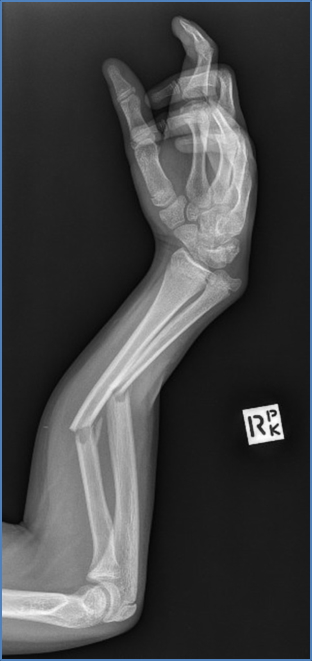

Upper Limb Fractures

- Mid-shaft Humerus → Radial nerve (via radial groove)

- Distal Radius (Colles’) Fracture → Median nerve, Ulnar nerve, Radial artery

- Combined Radius & Ulna Wrist Fracture → Median and Ulnar nerves, Radial and Ulnar arteries

- Volar (Palmar) Wrist Laceration — Often seen in penetrating trauma (e.g. suicide attempts)

- Median nerve

- Ulnar nerve

- Radial and ulnar arteries

- Basilic and cephalic veins

- Wrist flexor tendons